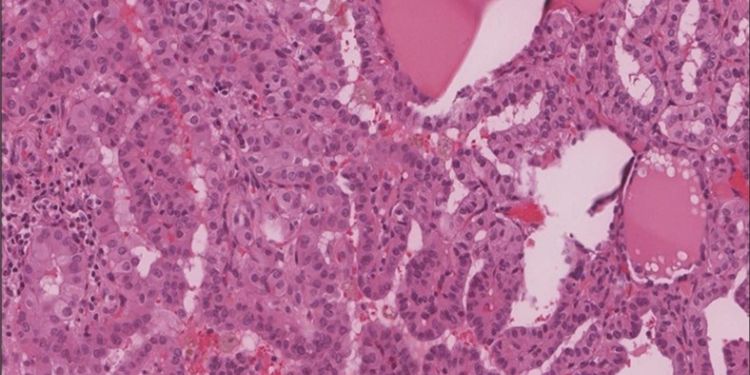

RET 898-901Del mutant, a variant of unknown significance, has a durable response to Pralsetinib in a Medullary Thyroid Carcinoma patient

DOI: 10.14302/issn.2574-4496.jtc-23-4722

Published on 30 Sep 2023

Read the full article